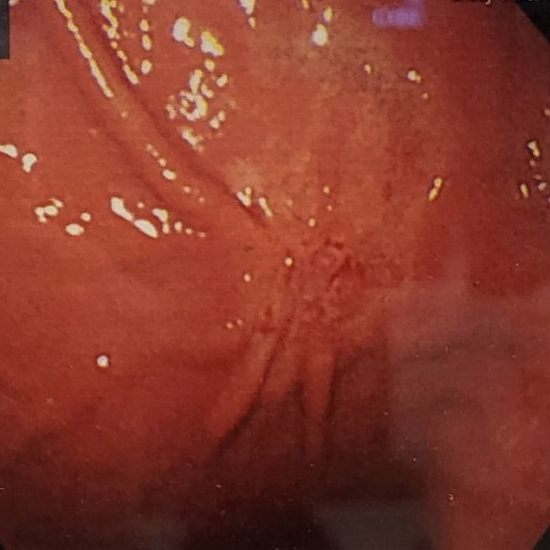

위궤양과 십이지장궤양